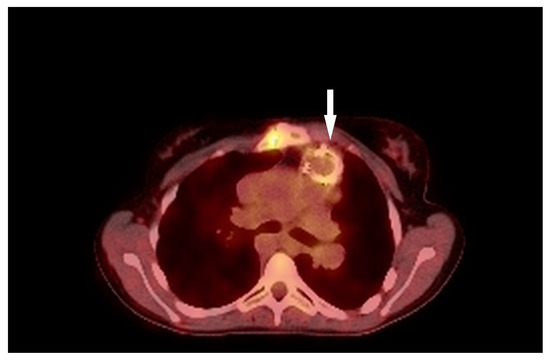

3.1. Case 1

3.2. Case 2

3.3. Case 3

3.4. Case 4